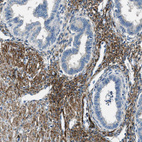

Immunohistochemistry analysis in human skeletal muscle and liver tissues using HPA018904 antibody. Corresponding SPEG RNA-seq data are presented for the same tissues.